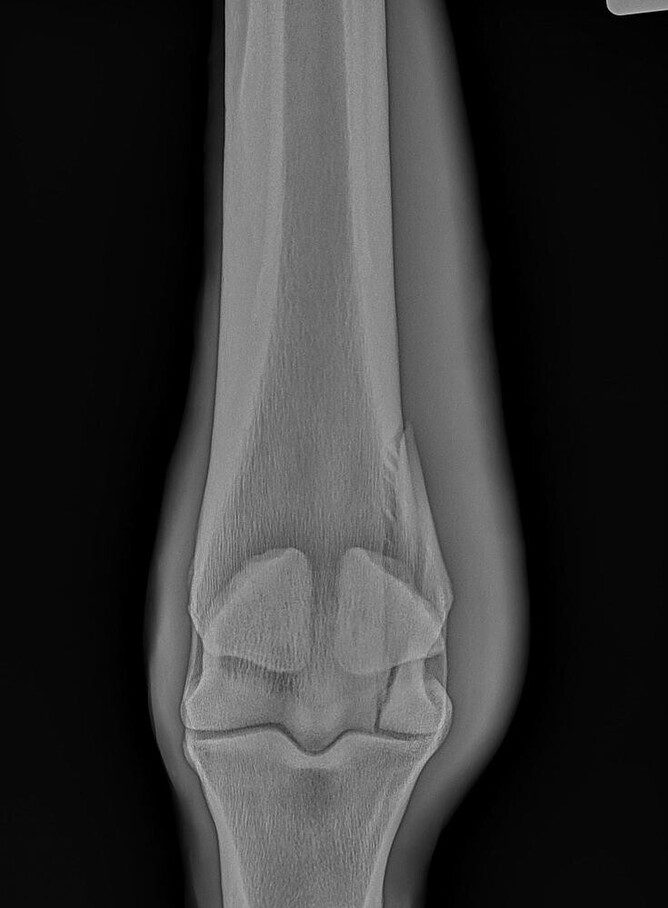

A röntgenvizsgálat nélkülözhetetlen a csontok és ízületek állapotának pontos felmérésében, legyen szó sérülések, fejlődési rendellenességek vagy degeneratív elváltozások diagnosztikájáról. Modern, digitális röntgenkészülékünk biztosítja a iváló minőségű képeket, amelyek alapján hatékony kezelési tervet dolgozhatunk ki.

- Sérülések diagnosztikája

- Sántaság, mozgásszervi problémák felderítése